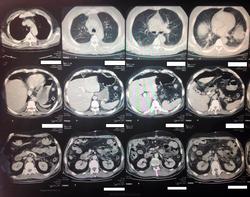

Пол пациента: Мужской пол Тип патологии: Злокачественное новообразование Область исследования: Грудная клетка и верхние дыхательные путиПищеварительная система Методы исследования: КТ к сожалению, ни анамнеза, ни жалоб у меня нет. только снимок. :( https://radiomed.ru/sites/default/files/styles/case_slider_image/public/user/19300/image_3_3.jpeg?itok=llGvHF8A https://radiomed.ru/sites/default/files/styles/case_slider_image/public/user/19300/image_1_3.jpeg?itok=m4fSrbr0 ID:33623 Пнд, 25/11/2013 - 16:58 #1 Петр Николаевич Не на сайте Был на сайте: 2 месяцев 2 недели назад Зарегистрирован: 15.03.2011 - 13:22 Публикации: 150 С чем разбираться? где снимки? Пнд, 25/11/2013 - 17:09 #2 Emchike Не на сайте Был на сайте: 10 лет 3 месяцев назад Зарегистрирован: 25.11.2013 - 14:06 Публикации: 4 анонимизированные изображенияПриложения: Пнд, 25/11/2013 - 17:12 #3 Helios Не на сайте Был на сайте: 1 год 2 недели назад Зарегистрирован: 06.08.2010 - 15:16 Публикации: 4417 Вот так-то лучше , но не совсем.Во-первых, жалобы, анамнез.Во-вторых, лучше дайкомы. Пнд, 25/11/2013 - 19:34 #4 Андрей Юрьевич Не на сайте Был на сайте: 2 недели 4 дня назад Зарегистрирован: 16.11.2008 - 22:16 Публикации: 18106 По тому, что видно - малый двусторонний гидроторакс. Андрей Юрьевич Пнд, 25/11/2013 - 19:50 #5 алкс Не на сайте Был на сайте: 10 лет 5 месяцев назад Зарегистрирован: 24.10.2012 - 22:55 Публикации: 2915 Андрей Юрьевич wrote: По тому, что видно - малый двусторонний гидроторакс. + Но это НЕ МРТ! Втр, 26/11/2013 - 00:38 #6 Emchike Не на сайте Был на сайте: 10 лет 3 месяцев назад Зарегистрирован: 25.11.2013 - 14:06 Публикации: 4 спасибо Втр, 26/11/2013 - 01:54 #7 Thirteenth Не на сайте Был на сайте: 11 лет 10 месяцев назад Зарегистрирован: 26.11.2013 - 01:51 Публикации: 3 Сдается мне, что в брюшной полости свободный возхдух - перфорация полого органа?

По тому, что видно - малый двусторонний гидроторакс.

Сдается мне, что в брюшной полости свободный возхдух - перфорация полого органа?